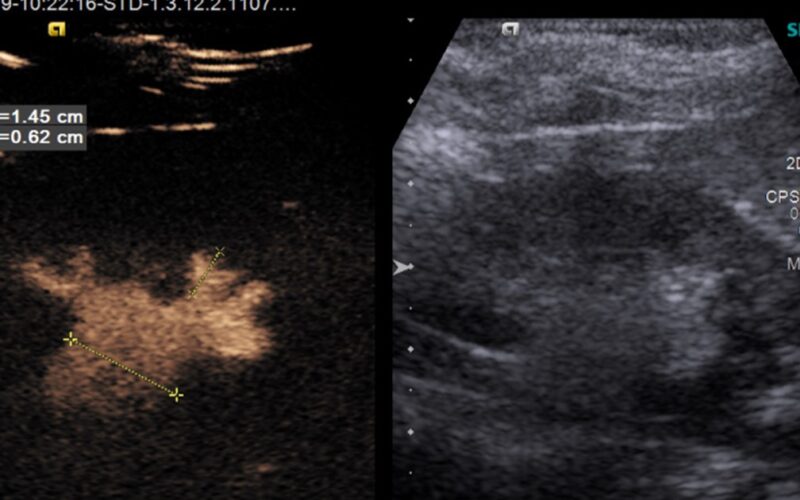

Ultrazvučna kontrastna mikciona urografija – cistografija (CeVus) je visoko osetljiv dijagnostički postupak u otkrivanju veziokoureteralnog refluksa, koji je u dečijem uzrastu najčešći uzrok ponovljenih urinarnih infekcija.

Ova metoda koristi ultrazvučno kontrastno sredstvo koje se direktno kateterskom tehnikom plasira u mokraćnu bešiku i na taj način omogućava praćenje kontrastnog sredstva, BEZ primene jonizujućeg zračenja.